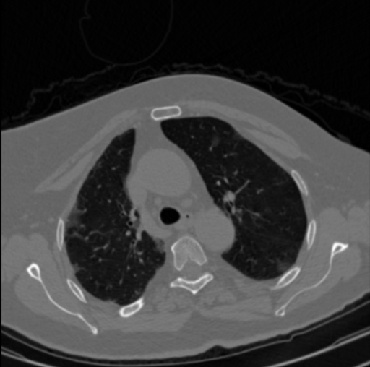

Early and reliable COVID-19 diagnosis based on chest 3-D CT scans can assist medical specialists in vital circumstances. Deep learning methodologies constitute a main approach for chest CT scan analysis and disease prediction. However, large annotated databases are necessary for developing deep learning models that are able to provide COVID-19 diagnosis across various medical environments in different countries. Due to privacy issues, publicly available COVID-19 CT datasets are highly difficult to obtain, which hinders the research and development of AI-enabled diagnosis methods of COVID-19 based on CT scans. In this paper we present the COV19-CT-DB database which is annotated for COVID-19, consisting of about 5,000 3-D CT scans, We have split the database in training, validation and test datasets. The former two datasets can be used for training and validation of machine learning models, while the latter will be used for evaluation of the developed models. We also present a deep learning approach, based on a CNN-RNN network and report its performance on the COVID19-CT-DB database.